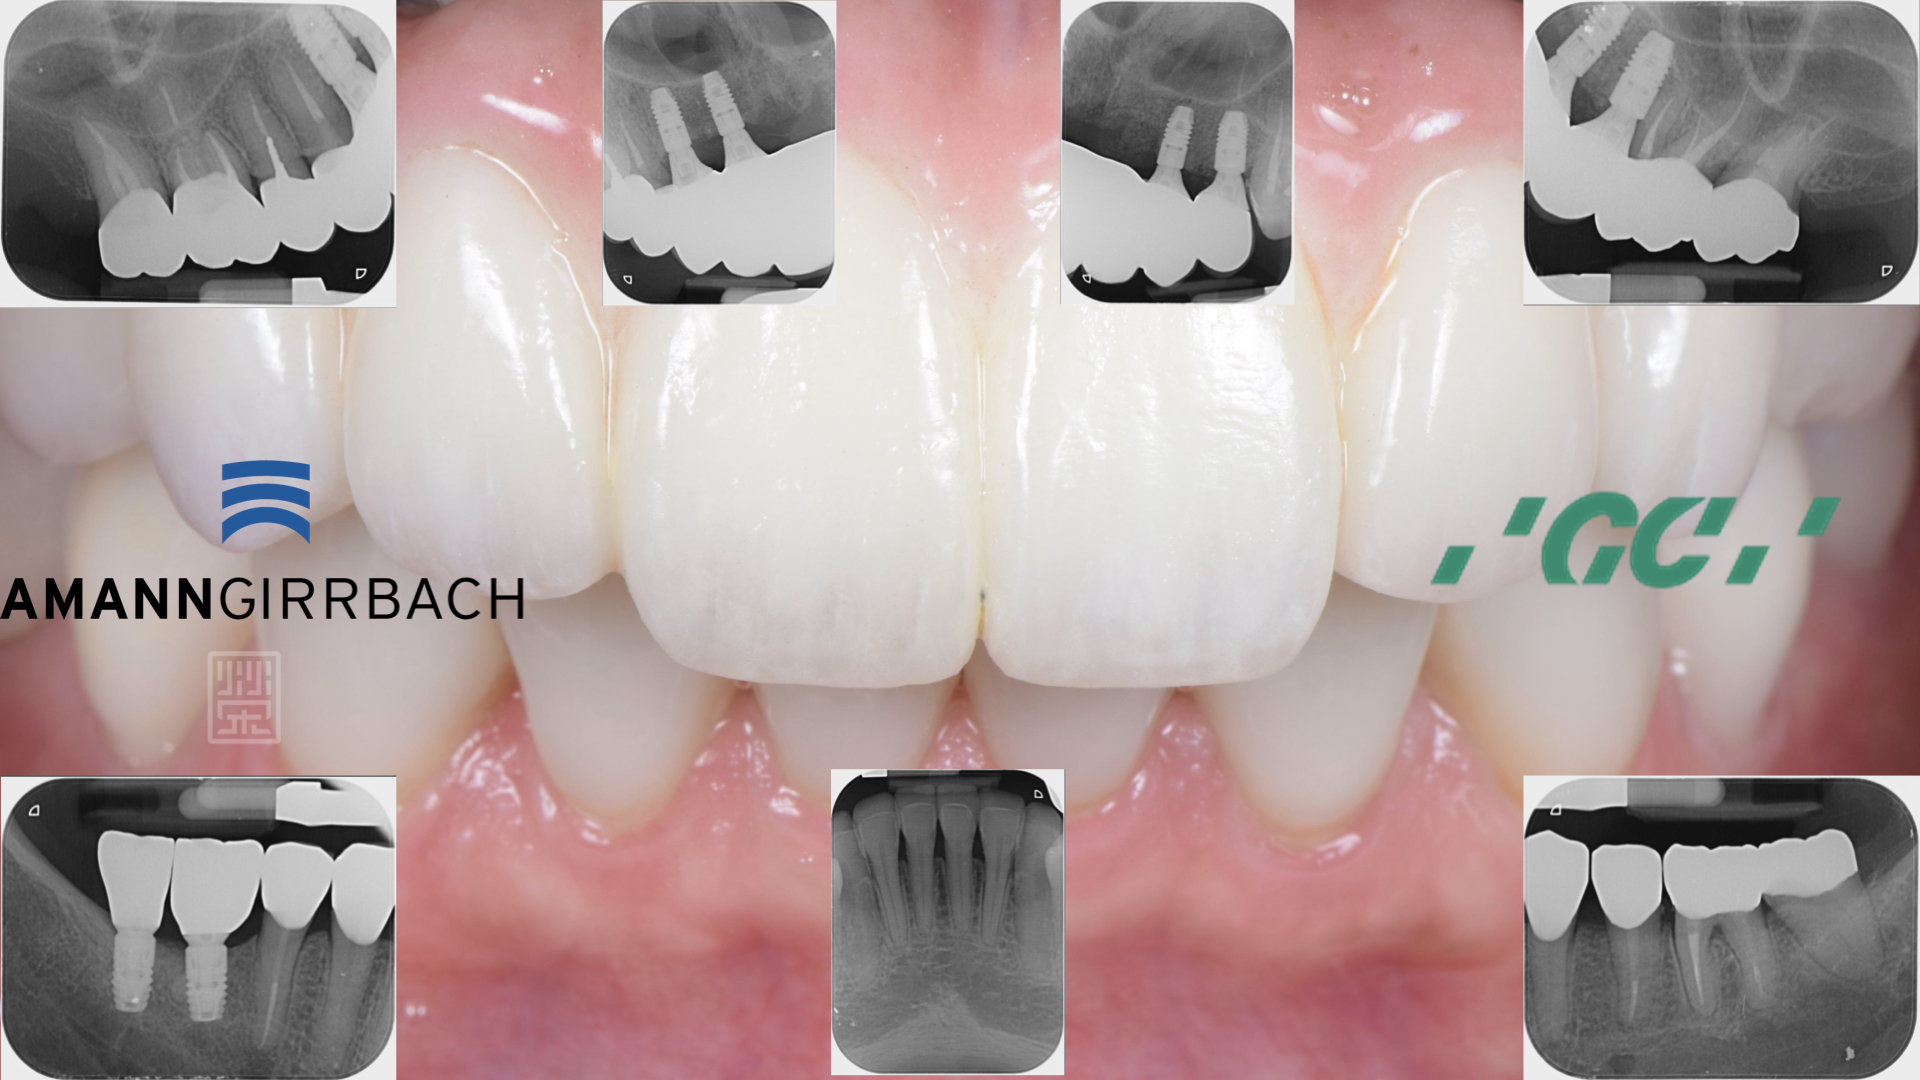

X光片中可以看到,多顆牙齒牙根蛀牙斷裂,牙套周圍二次蛀牙,根尖發炎

X光檢查下,全瓷贋復物與牙齒秘貼性良好,讓清潔容易好維持

全瓷贋復物完成